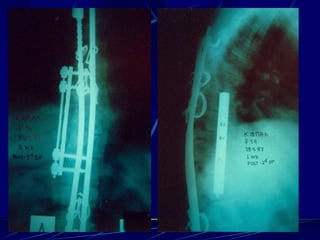

Post-operative infections